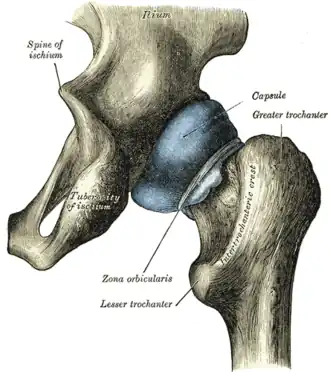

Left hip-joint, opened by removing the floor of the acetabulum from within the pelvis.

In human anatomy, the lesser trochanter is a conical, posteromedial, bony projection from the shaft of the femur. It serves as the principal insertion site of the iliopsoas muscle.[1]

The lesser trochanter is a conical posteromedial projection of the shaft of the femur, projecting from the posteroinferior aspect of its junction with the femoral neck.[1]

The summit of the lesser trochanter gives insertion to the tendon of the psoas major muscle and the iliacus muscle;[3] the lesser trochanter represents the principal attachment of the iliopsoas.[1]

The intertrochanteric crest (which demarcates the junction of the femoral shaft and neck posteriorly) extends between the lesser trochanter and the greater trochanter on the posterior surface of the femur.[1]